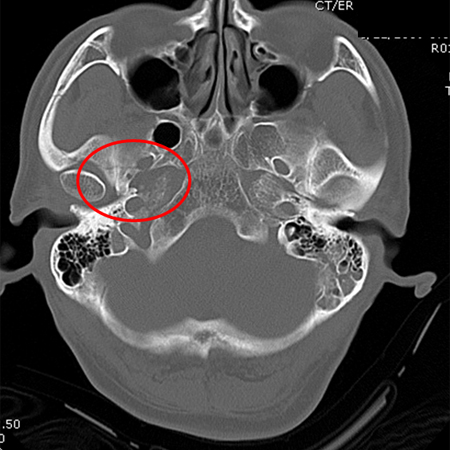

Fracture of temporal bone extending into foramen ovale

From the teaching collection of Demetrios Demetriades; used with permission